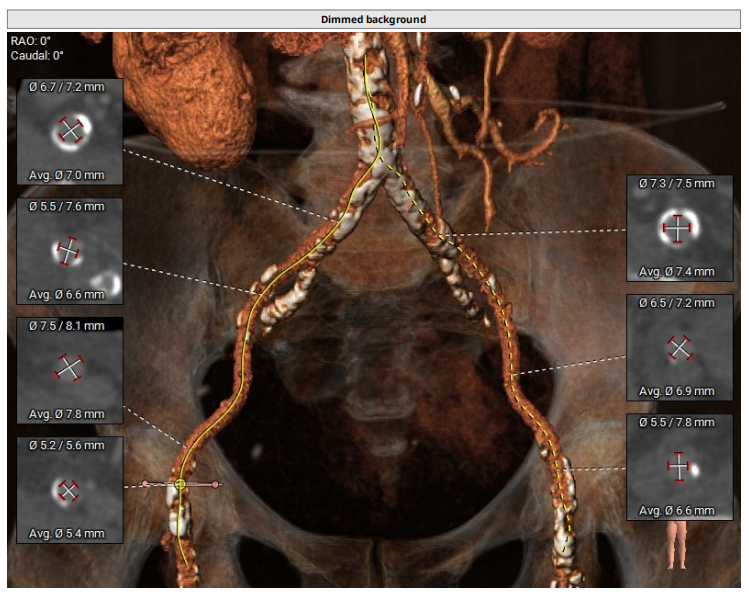

入路情况:

主动脉弓降部走行欠佳,弓顶部可见钙化,术中操作需谨慎,主动脉弓部三根毛开口未见明显狭窄征象、未见发育异常,胸主动脉、腹主动脉走行较平直,可见多发钙化,类瓷化主动脉,管腔未见明显狭窄征象,双侧髂动脉-股动脉走行稍迂曲,可见多发钙化,部分呈半环形、马蹄形、环形分布,管腔未见明显狭窄征象,若尝试股动脉入路,考虑血管并发症风险,术中操作需尽量轻柔,注意规避穿刺点附近血管前壁钙化,右侧股动脉穿刺水平管腔直径约7.8mm,右侧股动脉分叉约在股骨头下方。